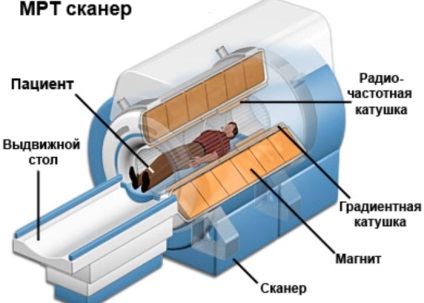

Folosit pentru aparat MRI este, în esență, o țeavă mare sub forma unui cilindru înconjurat de un magnet. Pacientul se află în jos pe o masă specială, care a efectuat sondajul. Tabelul este retras în interiorul tubului. În timp ce unele unități absorb complet tabel, în timp ce altele sunt doar parțial sau nu toate părțile deschise. Pacientul este fixat pe masa fertiliza role și curele.

În camera de zi este tot echipamentul care primește informații de la dispozitiv. Magnet emite unde radio și, prin urmare, nu cauzează nici un pericol pentru om. Semnalele rezultate sunt procesate și transformate într-un anumit număr de fotografii.